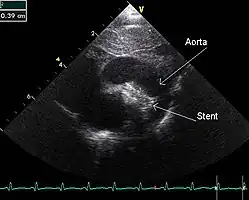

An echocardiogram of a stented persisting ductus arteriosus: One can see the aortic arch and the stent leaving. The pulmonary artery is not seen. -